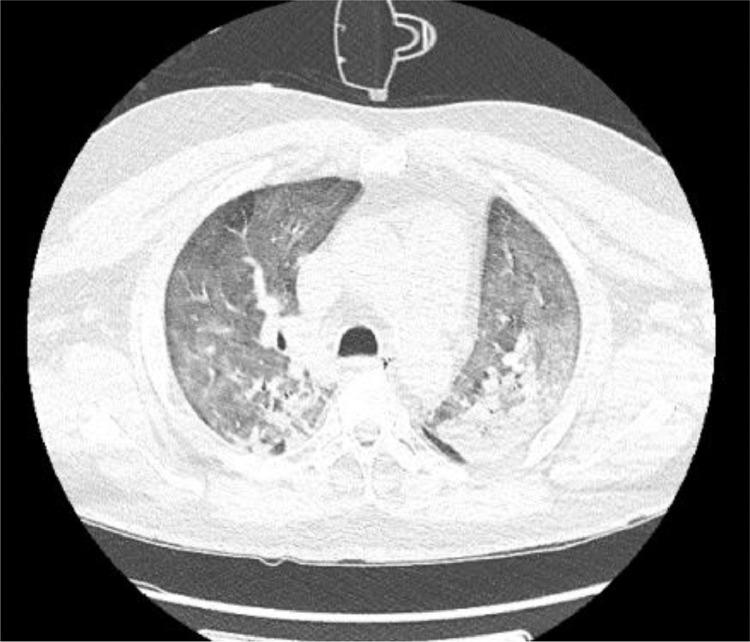

Severe acute respiratory syndrome coronavirus (SARS-CoV-2) is responsible for an unprecedented worldwide pandemic that has severely impacted the United States. As the pandemic continues, a growing body of evidence suggests that infected patients may develop significant coagulopathy with resultant thromboembolic complications including deep vein thrombosis, pulmonary embolism, myocardial infarction, and ischemic stroke. However, this data is limited and comes from recent small case series and observational studies on stroke types, mechanisms, and outcomes. Furthermore, evidence on the role of therapeutic anticoagulation in SARS-CoV-2 infected patients with elevated inflammatory markers, such as D-dimer, is also limited. We report the case of a middle-aged patient who presented with a large vessel ischemic stroke likely resulting from an underlying inflammatory response in the setting of known novel coronavirus infection (COVID-19). Histopathologic analysis of the patient's ischemic brain tissue revealed hypoxic neurons, significant edema from the underlying ischemic insult, fibrin thrombi in small vessels, and fibroid necrosis of the vascular wall without any signs of vasculature inflammation. Brain biopsy was negative for the presence of SARS-CoV-2 RNA (RT-PCR assay). Along with a growing body of literature, our case suggests that cerebrovascular thromboembolic events in COVID-19 infection may be related to acquired hypercoagulability and coagulation cascade activation due to the release of inflammatory markers and cytokines, rather than virus-induced vasculitis. Further studies to investigate the mechanism of cerebrovascular thromboembolic events and their prevention is warranted.

严重急性呼吸综合征冠状病毒(SARS-CoV-2)引发了一场史无前例的全球大流行,对美国造成了严重影响。随着大流行的持续,越来越多的证据表明,感染患者可能会出现明显的凝血功能障碍,导致血栓栓塞并发症,包括深静脉血栓形成、肺栓塞、心肌梗死和缺血性卒中。然而,这些数据有限,并且来自最近关于卒中类型、机制和结果的小病例系列和观察性研究。此外,关于在炎症标志物(如 D-二聚体)升高的 SARS-CoV-2 感染患者中使用抗凝治疗的证据也有限。我们报告了一例中年患者的病例,该患者患有大血管缺血性卒中,可能是在已知新型冠状病毒(COVID-19)感染的情况下,由潜在的炎症反应引起的。对患者缺血性脑组织的组织病理学分析显示,缺氧神经元、潜在缺血损伤引起的明显水肿、小血管中的纤维蛋白血栓形成以及血管壁的纤维样坏死,没有任何血管炎症的迹象。脑活检未发现 SARS-CoV-2 RNA(RT-PCR 检测)的存在。随着越来越多的文献报道,我们的病例表明,COVID-19 感染中的脑血管血栓栓塞事件可能与炎症标志物和细胞因子的释放导致的获得性高凝状态和凝血级联激活有关,而不是病毒引起的血管炎。有必要进一步研究脑血管血栓栓塞事件的发生机制及其预防措施。